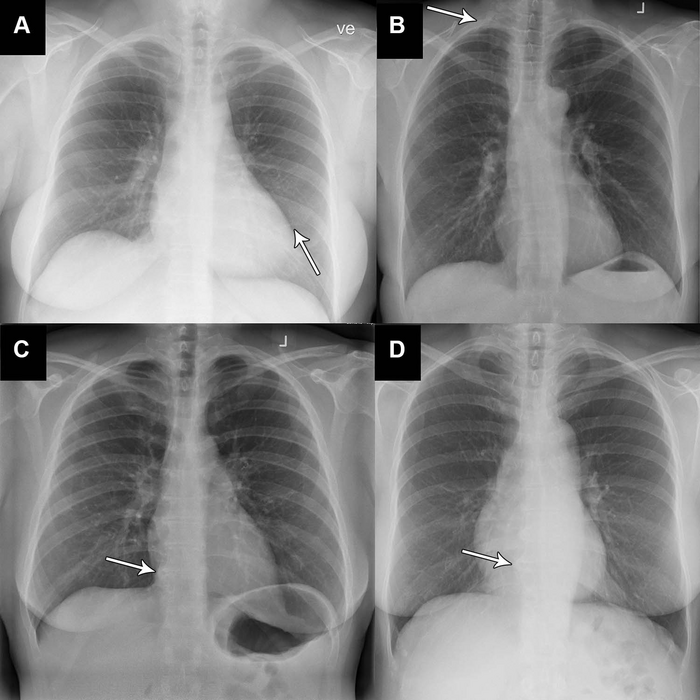

Basic Chest XRay Interpretation Tips and pointers to see it all!